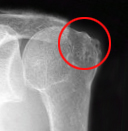

X線(レントゲン)所見では、肩峰や上腕骨の変形や、肩峰と骨頭間距離などにより評価をします。